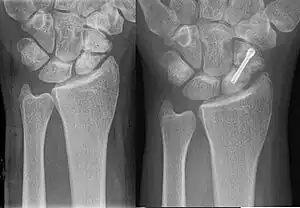

![]() | |

| An X-ray showing a fracture through the waist of the scaphoid | |

A more obvious scaphoid fracture on a scaphoid view X ray